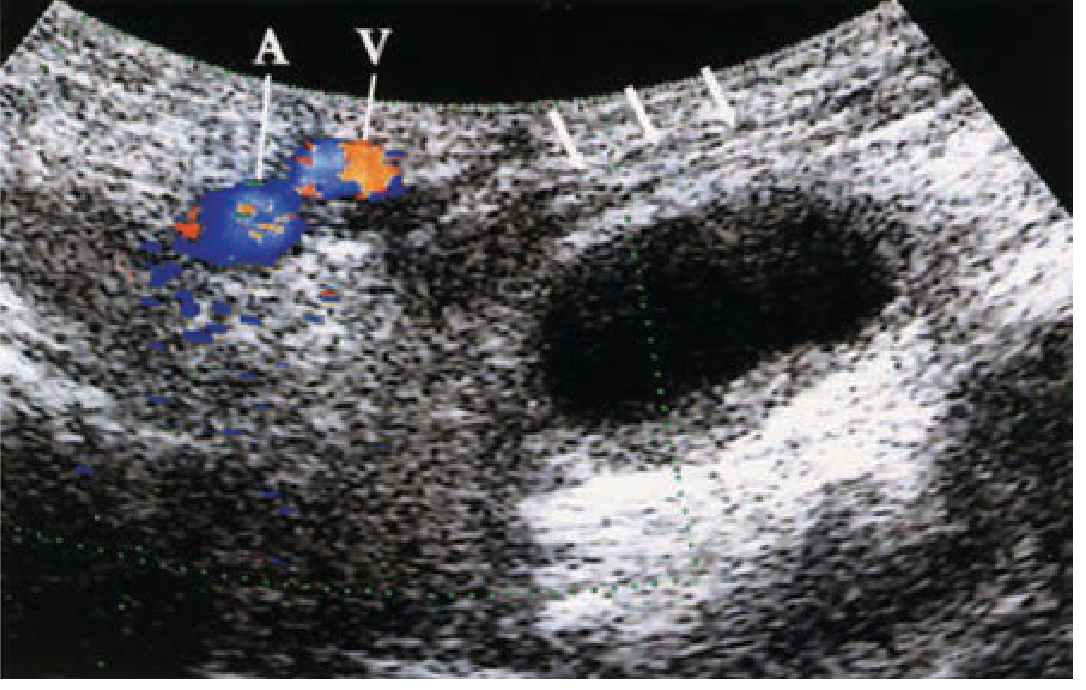

| Femoral artery aneurysm | Fusiform/saccular dilation with turbulent flow on Doppler |

| Saphena varix | Compressible cystic structure at saphenofemoral junction, fills on Valsalva |